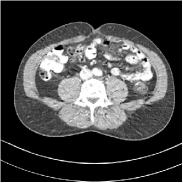

This special case of SUPER corresponds to the case where SUPER excludes the unsupervised regularizer, while only involves the data-fidelity and a supervised regularizer in the MBIR cost, i.e., β=0𝛽0\beta=0 and μ0𝜇0\mu\neq 0. In this case, the proposed SUPER model is similar to a generalized block coordinate descent-based network by replacing a simple denoising autoencoder [28, 29, 30] with a general CNN that forms our supervised regularizer. This SUPER is also similar to the plug-and-play ADMM-Net method except that the inputs to each supervised network are the preceding reconstructions, while plug-and-play ADMM-Net updates inputs to the network (denoiser) based on auxiliary variables in the ADMM algorithm. Here, we used μ=1×106𝜇1superscript106\mu=1\times 10^{6}, which worked well for the plug-and-play ADMM-Net method, for this special case of SUPER. Fig. 7 shows a comparison between plug-and-play ADMM-Net, SUPER without unsupervised regularizers (in both training and testing), and the full SUPER version with ULTRA regularization (β=5×103𝛽5superscript103\beta=5\times 10^{3}, μ=5×105𝜇5superscript105\mu=5\times 10^{5}). All these methods used WavResNet as their denoisers/supervised networks. In this example, SUPER with only a supervised regularizer (SUPER-WRN-β=0𝛽0\beta=0) outperforms the plug-and-play ADMM-Net (ADMM-Net (WRN)) by 1.6 HU RMSE and provides sharper image details. Comparing SUPER-WRN-β=0𝛽0\beta=0 and the full SUPER-WRN-ULTRA scheme, we observe that the latter provides a lower RMSE and higher contrast image features than the former that excludes the unsupervised component. This again shows the effect of the unsupervised ULTRA model (in capturing local image details better with a union of learned transforms) in the SUPER scheme.

Refer to captionADMM-Net (WRN)RMSE = 32.90 HURefer to captionADMM-Net (WRN)RMSE = 32.90 HU

Refer to captionSUPER-WRN-β=0𝛽0\beta=0RMSE = 31.32 HURefer to captionSUPER-WRN-β=0𝛽0\beta=0RMSE = 31.32 HU

Refer to caption SUPER-WRN-ULTRARMSE = 29.74 HURefer to caption SUPER-WRN-ULTRARMSE = 29.74 HU

Refer to caption ReferenceRefer to caption Reference

Figure 7: Reconstructed images of L192 slice 150 with WavResNet plugged ADMM-Net, SUPER-WRN-β=0𝛽0\beta=0 (both training and testing), and SUPER-WRN-ULTRA (β=5×103𝛽5superscript103\beta=5\times 10^{3} in both training and testing), respectively, shown with the reference image.